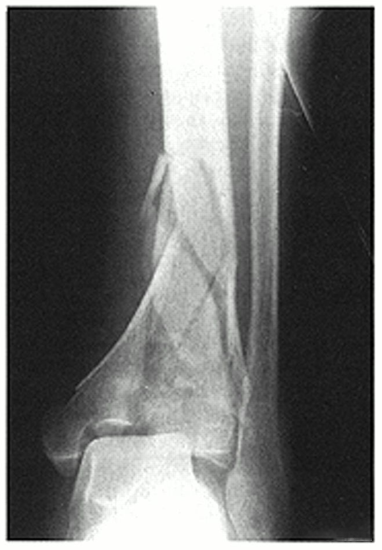

(5)Maisonneuve 骨折

法国医生 Maisonneuve 是 Dupuytren 的学生,他在 1840 年首次提出外旋暴力导致了一种特殊类型的踝关节骨折,即 Maisonneuve 骨折。Maisonneuve 骨折约占踝部损伤的 1%~11%, 属于踝关节骨折 Lauge-Hansen 分型中的旋前 - 外旋型 Ⅲ 度以上的损伤。Weber 分型为 C 型。